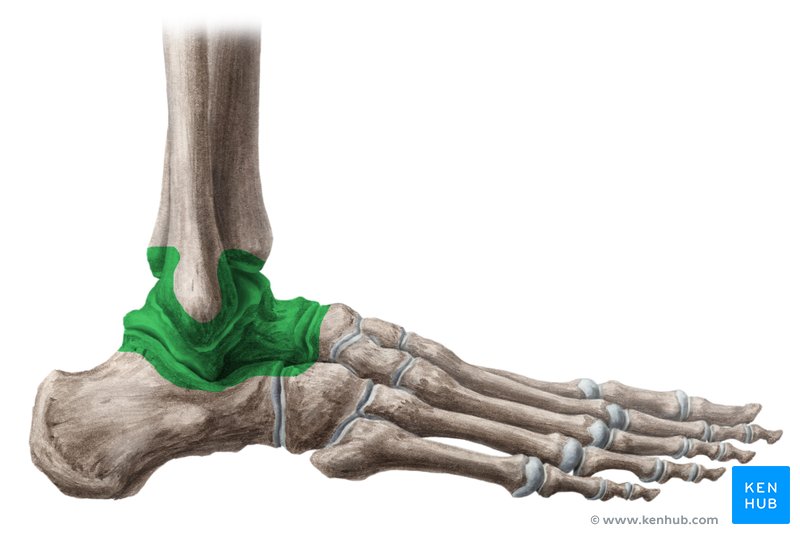

what is the deltoid ligament?

what does the deltoid ligament do?

restrict eversion

what are the medial ligaments of the deltoid ligament?

anterior tibiotalar

tibionavicular

tibiocalcaneal

posterior tibiotalar